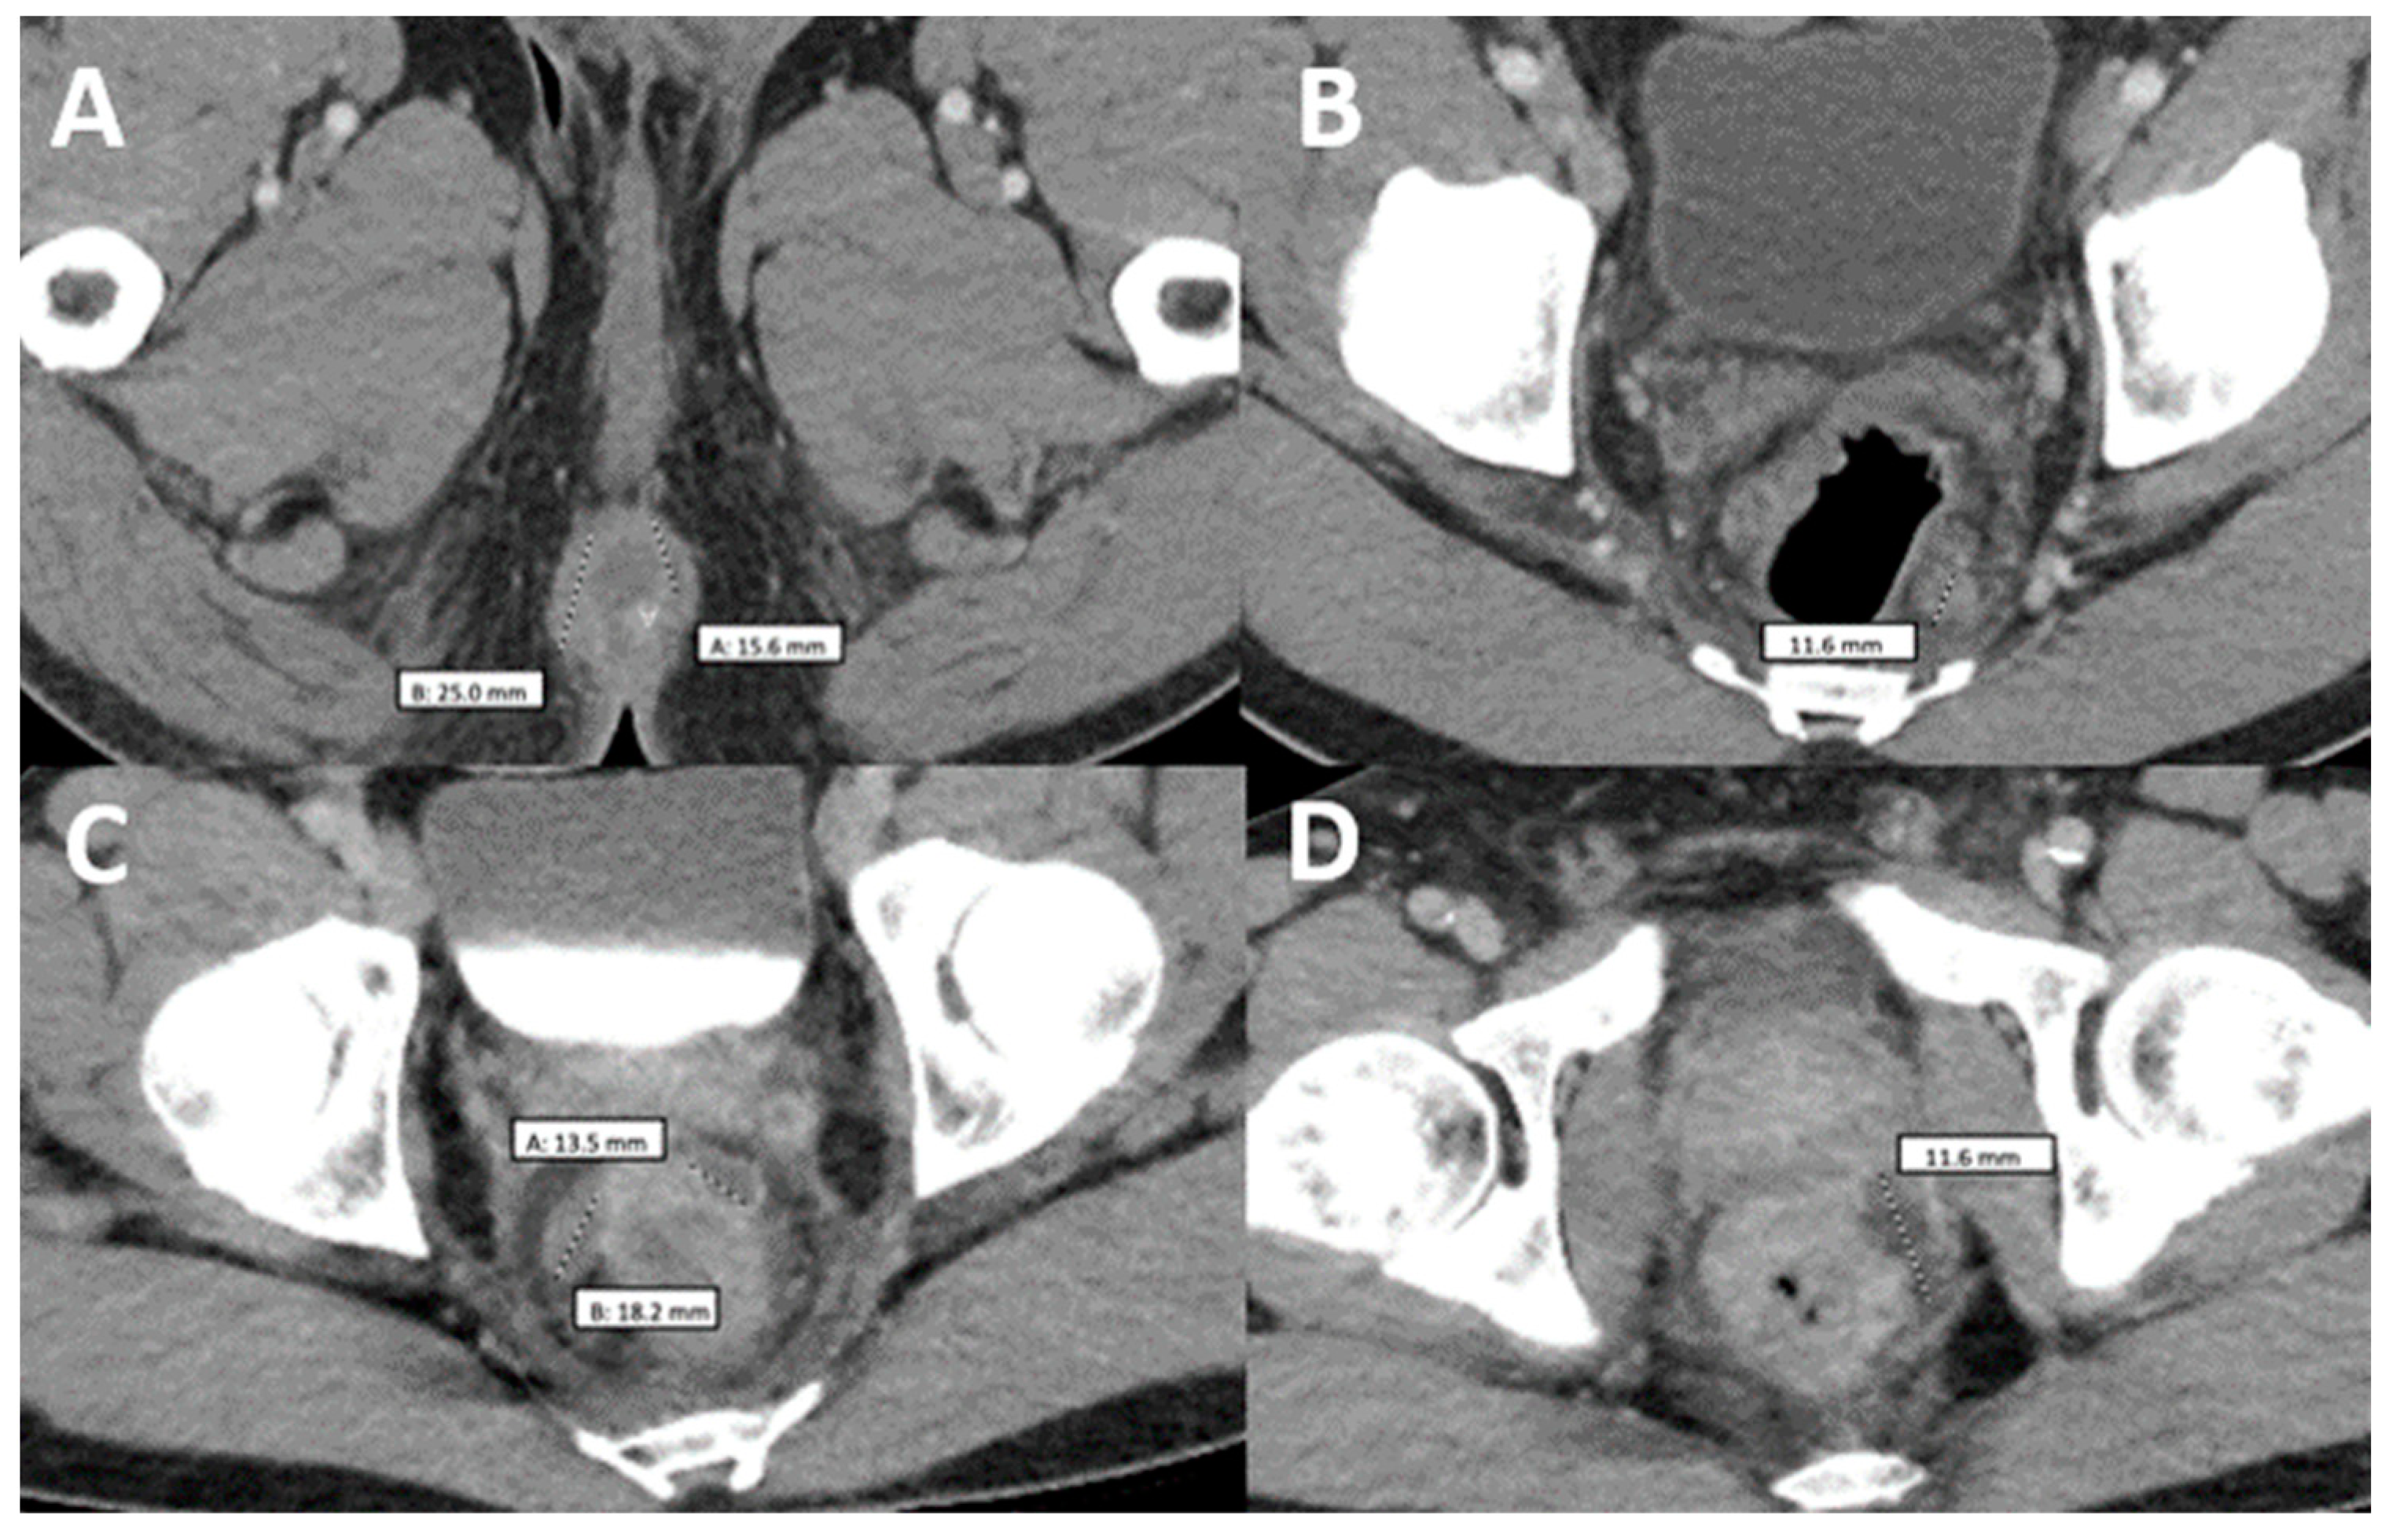

Figure 1.

Patient presenting with monkeypox dermatological lesions: (A) Initial presentation without any previous treatment. (B) Improvement after treatment with tecovirimat. (C) Worsening of his monkeypox with hemorrhagic lesions with crusting in the center and whitish discoloration around them after 15 days of ART initiation. (D) White-yellow rounded punched-out erosions on the perianal region with elevated borders and surrounding purulent material. (E) Temporal lesion. (F,G) Worsening nasal lesions 42 days after ART initiation. (H) Abscess in the left ankle. (I) Face lesions after 1st Cidofovir dose. (J) Progression of the temporal lesion. (K) Lesions improving and crusted, close to discharge.

Two weeks later, the patient was seen at the Florida DOH and was started on tecovirimat 600 mg PO twice daily due to the progression and dissemination of his initial lesions. One week later, the patient returned to our ED, reporting burning pain with purulent discharge from his rectum. On examination, he had more than 25 skin lesions distributed on his face, scalp, mouth, chest, back, perineum and extremities. These lesions consisted of large confluent vesicles with central umbilication and ulceration (Figure 1A,B). The patient agreed to HIV screening, which was reactive. Further laboratory testing showed a CD4 count of 218 cells/mcL (CD4 percentage of 7.60%) and a viral load of 85,300 copies/mL. A pelvic CT scan was done, showing a 2.5 cm perirectal abscess. He was not tested for other sexually transmitted diseases during this admission. Antibiotic therapy with ceftriaxone and metronidazole was initiated for a presumptive superimposed bacterial rectal abscess. Treatment with tecovirimat continued as previously planned. After 4 days of therapy, the patient had an improvement in symptoms, including his skin lesions (Figure 1B). He was discharged on tecovirimat to complete 14 days of therapy along with a course of 7 days of amoxicillin-clavulanic acid for his abscess. Additionally, he was started on ART as an outpatient with TAF/emtricitabine/bictegravir.

Two weeks later and 6 weeks after the initial presentation, the patient returned to the ED after 5 days of the worsening of the existing Mpox lesions, bilateral periorbital edema, facial pain, and increasingly severe rectal pain. Of note, this was 15 days after starting ART and after completing the first course of tecovirimat for 14 days. Upon physical exam, he had numerous vesicles and pustules with central umbilication and necrotic crusting on his face (Figure 1C,E). Over his prior active Mpox lesions, he had hyperpigmentation and collarettes of scales, signs of excoriation with surrounding erythema. On his perirectal region, several rounded punched-out erosions with surrounding purulent discharge (Figure 1D). A second course of tecovirimat was initiated due to disease progression in the setting of a prior improvement with tecovirimat. Repeat abdominal/pelvic CT showed multiple perirectal abscesses indicating proctitis of the entire rectosigmoid segment. He underwent testing with urinary gonorrhea and chlamydia PCR, which was positive only for chlamydia. Due to presumptive lymphogranuloma venereum (LGV) proctitis, chlamydia urethritis, and perirectal abscess, the patient was started on oral doxycycline for 21 days as well as oral metronidazole and levofloxacin (Figure 2). At this time, surgical drainage was deferred. After 5 days of hospitalization, the patient’s symptoms improved, and he was discharged on a second 14-day course of tecovirimat, along with his other antimicrobial regimens and prophylaxis.

Our patient initially came with classical mpox skin lesions and started improving after the first course of tecovirimat treatment (Figure 1B). Then, he was diagnosed with HIV and had borderline immunosuppression (CD4 count of 218 cells/mcL and a percentage of 7.60%) with subsequent ART initiation. However, the skin lesions took a paradoxical turn after 4 weeks and apparently, the only precipitant factor identified after extensive workup was ART. IRIS was previously described as a syndrome that affects patients with a low baseline CD4 count, below 100 cells/mcL for most infections except for tuberculosis which can occur regardless of the immune status [22,23]. Nevertheless, further studies have shown that there are other factors that can induce the response in non-lymphopenic patients, like the dysregulated antigen recognition when the repopulation happens, explained by the higher frequencies of effector memory, PD-1+, HLA-DR+, and Ki67+ CD4+ T cells/mcL [24]. For example, in a case report of a patient with HIV and IRIS-related Pneumocystis jiroveci pneumonia, the CD4 count was 370 cells/mcL [25]. Also, in the TB-HAART clinical trial, a cohort of more than 1500 patients diagnosed with tuberculosis and with a CD4+ count greater than 220 cells/mcL was evaluated, and a 10% incidence of tuberculosis-associated IRIS was found [26]. Furthermore, since the introduction of Integrase strand transfer inhibitors (InSTIs), the viral load can be more rapidly suppressed than the cases treated with other regimens accelerating the lymphocyte repopulation, and this can also explain why the syndrome happened so early in the disease course (15 days from ART initiation to first IRIS symptoms) [27]; however, a recent meta-analysis found that there is no overall increased incidence of IRIS when using InSTIs compared to alternative regimens [28]. Although there is no way how to confirm that the worsening of lesions on this patient corresponds to IRIS, it is highly suggestive that the initiation of ART may play a role in the worsening of pre-existent lesions and, thus, suggest paradoxical mpox IRIS in this population.